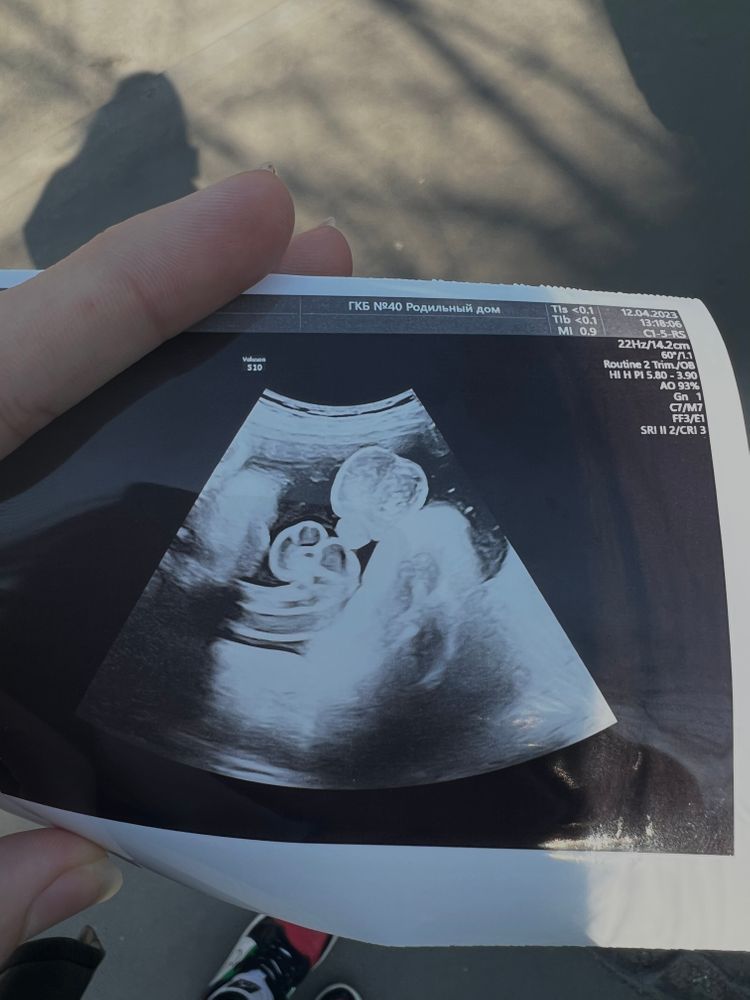

Шутка Узиста😹🫶🏻

Перед заключением контракта нужно было пройти предконтрактное обследование и туда сходит узи)

Мы ждём сына, причем, об этом нам сказали на первом скрининге) соответсвенно, купили уже все для мальчишки

итак, лежу я на кушетке, врач водит датчиком и такой:

-вы знаете кого ждете?

-да, конечно, мальчишку

-ну у вас не мальчик

-как???девочка?столько раз была на узи и всегда мальчик говорили

*секунд 20 всматривается в экран, водит датчиком*

-у вас не мальчик, у вас мужчина!

девочкиииии, сердце в пятки ушло😹😹😹

конечно я была бы рада любому исходу, вообще не принципиально было кто будет, но было бы удивительно узнать, что ждешь ребенка другого Пола прям перед родами😹